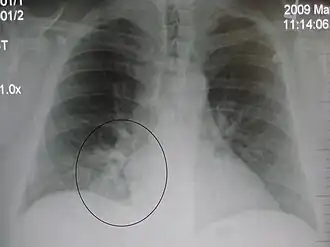

AP CXR showing left lower lobe pneumonia associated with a small left sided pleural effusion -

AP CXR showing right lower lobe pneumonia -

AP CXR showing pneumonia of the lingula of the left lung -

Right upper lobe pneumonia as marked by the circle. -

Left upper lobe pneumonia with a small pleural effusion.

The discovery of x-rays made it possible to determine the anatomic type of pneumonia without direct examination of the lungs at autopsy and led to the development of a radiological classification. Early investigators distinguished between typical lobar pneumonia and atypical (e.g. Chlamydophila) or viral pneumonia using the location, distribution, and appearance of the opacities they saw on chest x-rays. Certain x-ray findings can be used to help predict the course of illness, although it is not possible to clearly determine the microbiologic cause of a pneumonia with x-rays alone.